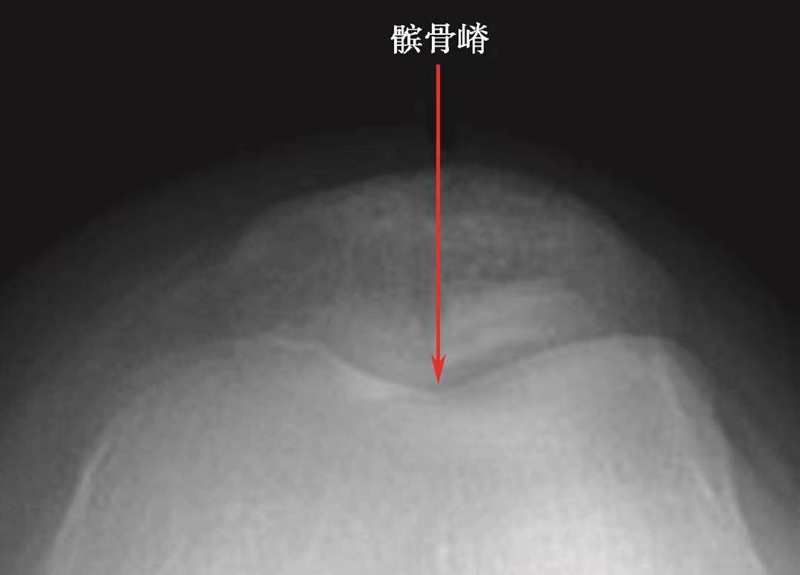

在髌骨轴位像上,髌骨的形态变化很大,Wiberg将髌骨形态分为3种类型(图9)。

图9 Wiberg分型示意图(红色箭头为WibergⅠ、Ⅱ、Ⅲ型的髌骨嵴所在位置)